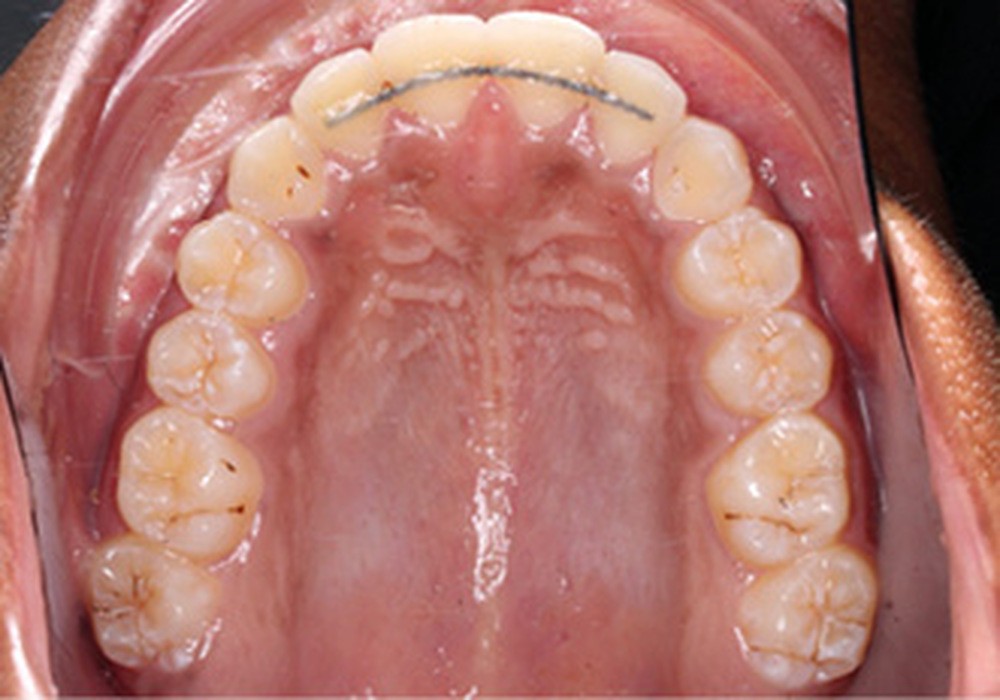

Examen clinique (fig. 1a-h)

L’arcade maxillaire est en V et la voûte palatine profonde. L’arcade mandibulaire a une forme en U (non-concordance des formes d’arcade) et présente des malpositions des dents cuspidées. La médiane mandibulaire est décalée à gauche de 2 mm ; le recouvrement antérieur est de 2 mm ; les molaires sont en classe III avec un surplomb inversé.

Un protocole ortho-chirurgical en chirurgie première a été retenu. Les étapes de traitement ont été les suivantes : motivation à l’hygiène bucco-dentaire et rééducation des fonctions, puis pose de l’appareil multi-attache edgewise conventionnel avec des arcs aciers .016x.022 passifs adaptés aux deux formes d’arcades, et enfin avancée de 6 mm et génioplastie d’avancée sur ces mêmes arcs.